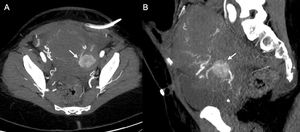

IatrogenicPseudoaneurysms account for 1.5% of vascular complications associated with diagnostic angiography and up to 6% after endovascular therapeutic procedures2 (Fig. 3). The incidence of complications related to vascular access puncture, including pseudoaneurysm, haematoma, arteriovenous fistula, thrombotic occlusion and extravasation, is 0.7–9%.2 They are related not only to the types of procedure, but also to the patient's underlying condition, to clinical and analytical decompensations secondary to the acute process, and to the medication the patient may be taking, such as anticoagulants or antiplatelet agents.2

29-year-old man on peritoneal dialysis with a history of renal transplant who had embolization of the transplanted kidney one month ago, and since then developed a mass in the right inguinal region where the puncture was made. Sagittal maximum intensity projection (A) and 3D (B) CT angiography reconstructions of the right lower limb in arterial phase showing a bilobed pseudoaneurysm (arrow) arising from the right common femoral artery.

Another cause of iatrogenic pseudoaneurysms is surgical interventions. They can occur as a complication of any type of surgery7,8 (Figs. 4–6). They arise from direct injury to the arteries in the vicinity of the surgical site or the approach routes. One example is those secondary to trocar management in laparoscopic surgery (Fig. 7).

A 58-year-old man who attended with a tumour-like lesion in the right inguinal region of one week’s duration following femoropopliteal bypass surgery. Coronal (A) and 3D (B) CT angiography reconstructions of the right thigh in arterial phase, showing a giant pseudoaneurysm (arrow) located at the anterior margin of the bifurcation of the common femoral artery, at the level of the proximal anastomosis of the femoropopliteal graft.